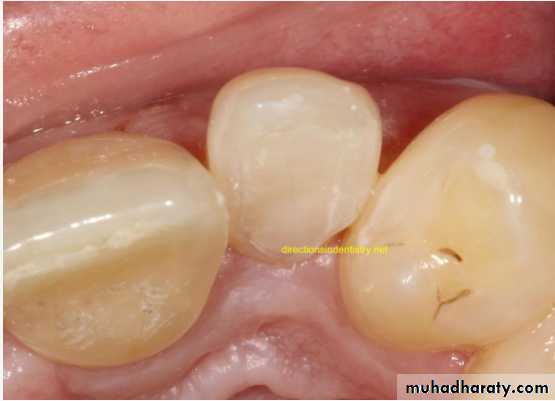

Dens in Dente (invaginated odontome) :

*It is an infolding of the outer surface of a tooth into the interior usually in the cingulum pit region of maxillary lateral incisors (tooth within a tooth).

*It is of 2 forms:coronal& radicular.

*Clinicaly varies from slight enlargement of cingulum

to a deep infolding that extends to the apex.

It has been classified into 3 major types:

*Type I:it is confined within the crown of the tooth and does not extend beyond the level of the external CEJ. *Type II :extends below CEJ ends in a blind sac, may or may not communicate with adjacent dental pulp. *Type III:extends through the root and communicates laterally with the periodontal ligament space through a pseudo-foramen or at the apical foramen . There is usually no communication with the pulp, which lies compressed within the root.*Most cases of dens in dente are discovered radiographically. It is more radiopaque than the surrounding tooth structure and can easily be identified.